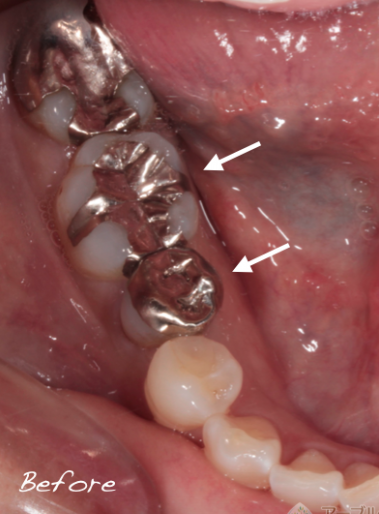

虫歯の治療を受ける場合は、患部の写真を撮って治療してもらえる歯科医院に行くことをオススメしています

当院では治療する場合は、口腔内写真を必ず撮影し、治療前と治療中、治療後で最低3枚以上撮影して、 治療後にどのような状態だったのか写真を撮って説明しています

問題が起きている歯や歯茎を口腔内専用カメラで撮影し治療前と治療後を比較。

治療後にモニターに映して説明しています。

治療途中も虫歯の取り残しがないことを記録で残しているため、治療後に歯に何か気になることがあっても過去の治療内容を見ることができるので安心です。

口腔内写真を取り、患部を拡大することにより、虫歯の取り残しを確実になくししています

以前治療した銀歯の内部から虫歯の取り残しが見つかった症例

最近治療した歯の内部から虫歯が見つかった症例

上記の写真はここまで虫歯になっていても痛みが全くない症例でした

治療を受ける際は、幹部の写真を撮影している歯科医院をお勧めしています

きちんと虫歯を治療しているかどうかはご自身の目で判断することが重要です

治療していると、過去に治療したレジン治療や銀歯治療の内部で虫歯の取り残しが多く見られます

治療を受ける際は、必ず内部で虫歯の取り残しがないかどうか自分の目で確認できる歯科医院を選択することをオススメしています